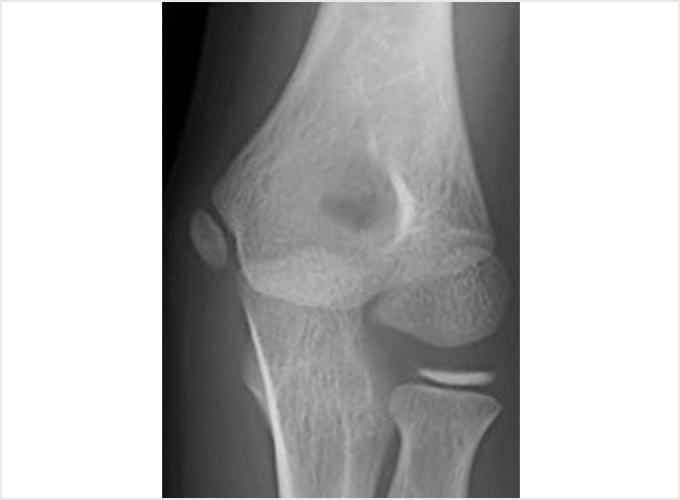

離断性骨軟骨炎(上腕骨小頭障害)

野球肘で最も重症になる障がいの1つです。ひどくなると関節軟骨の一部がはがれて関節ネズミとなったり、肘が変形して動きが悪くなったりします。初期に発見されれば投球禁止で治り、手術はしなくてもすむ場合が多いのですが、末期になると手術が必要となり、手術をしても肘の動きの制限や変形が残ってしまうこともあります。10歳前後で発症することが多いのですが、初期には自覚症状がないことが多く、13-17歳ごろにグラグラになった軟骨がはがれて痛みが出て初めて医療機関を受診されることもよくあります。 手術となった場合には骨の成長の度合い、病変の進行具合、病変の大きさなどにより手術方法が変わります。軟骨が安定している場合には軟骨を固定する手術を行う場合が多いです。軟骨がはがれている場合、病変が小さければ関節鏡を用いてはがれた、あるははがれかけている軟骨を摘出します(図4a)。病変の直径が1㎝以上であれば切開手術で膝の軟骨を病変部に移植します(図4b)。 最近全国各地で少年野球検診が行われるようになりましたが、一番の目的は離断性骨軟骨炎を早期に発見し、重症になる前に治療を行うことなのです。平成28年から多くの医師、理学療法士の協力により名古屋でも行われるようになりました。私も検診に参加し、エコーでのチェックを担当しました。およそ100人に1-2人の割合で発見されました。